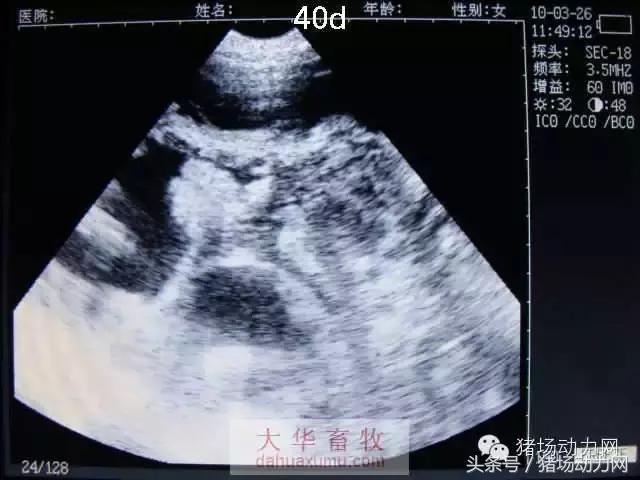

以下为怀孕母猪21天到90天之内的变化图:

40天